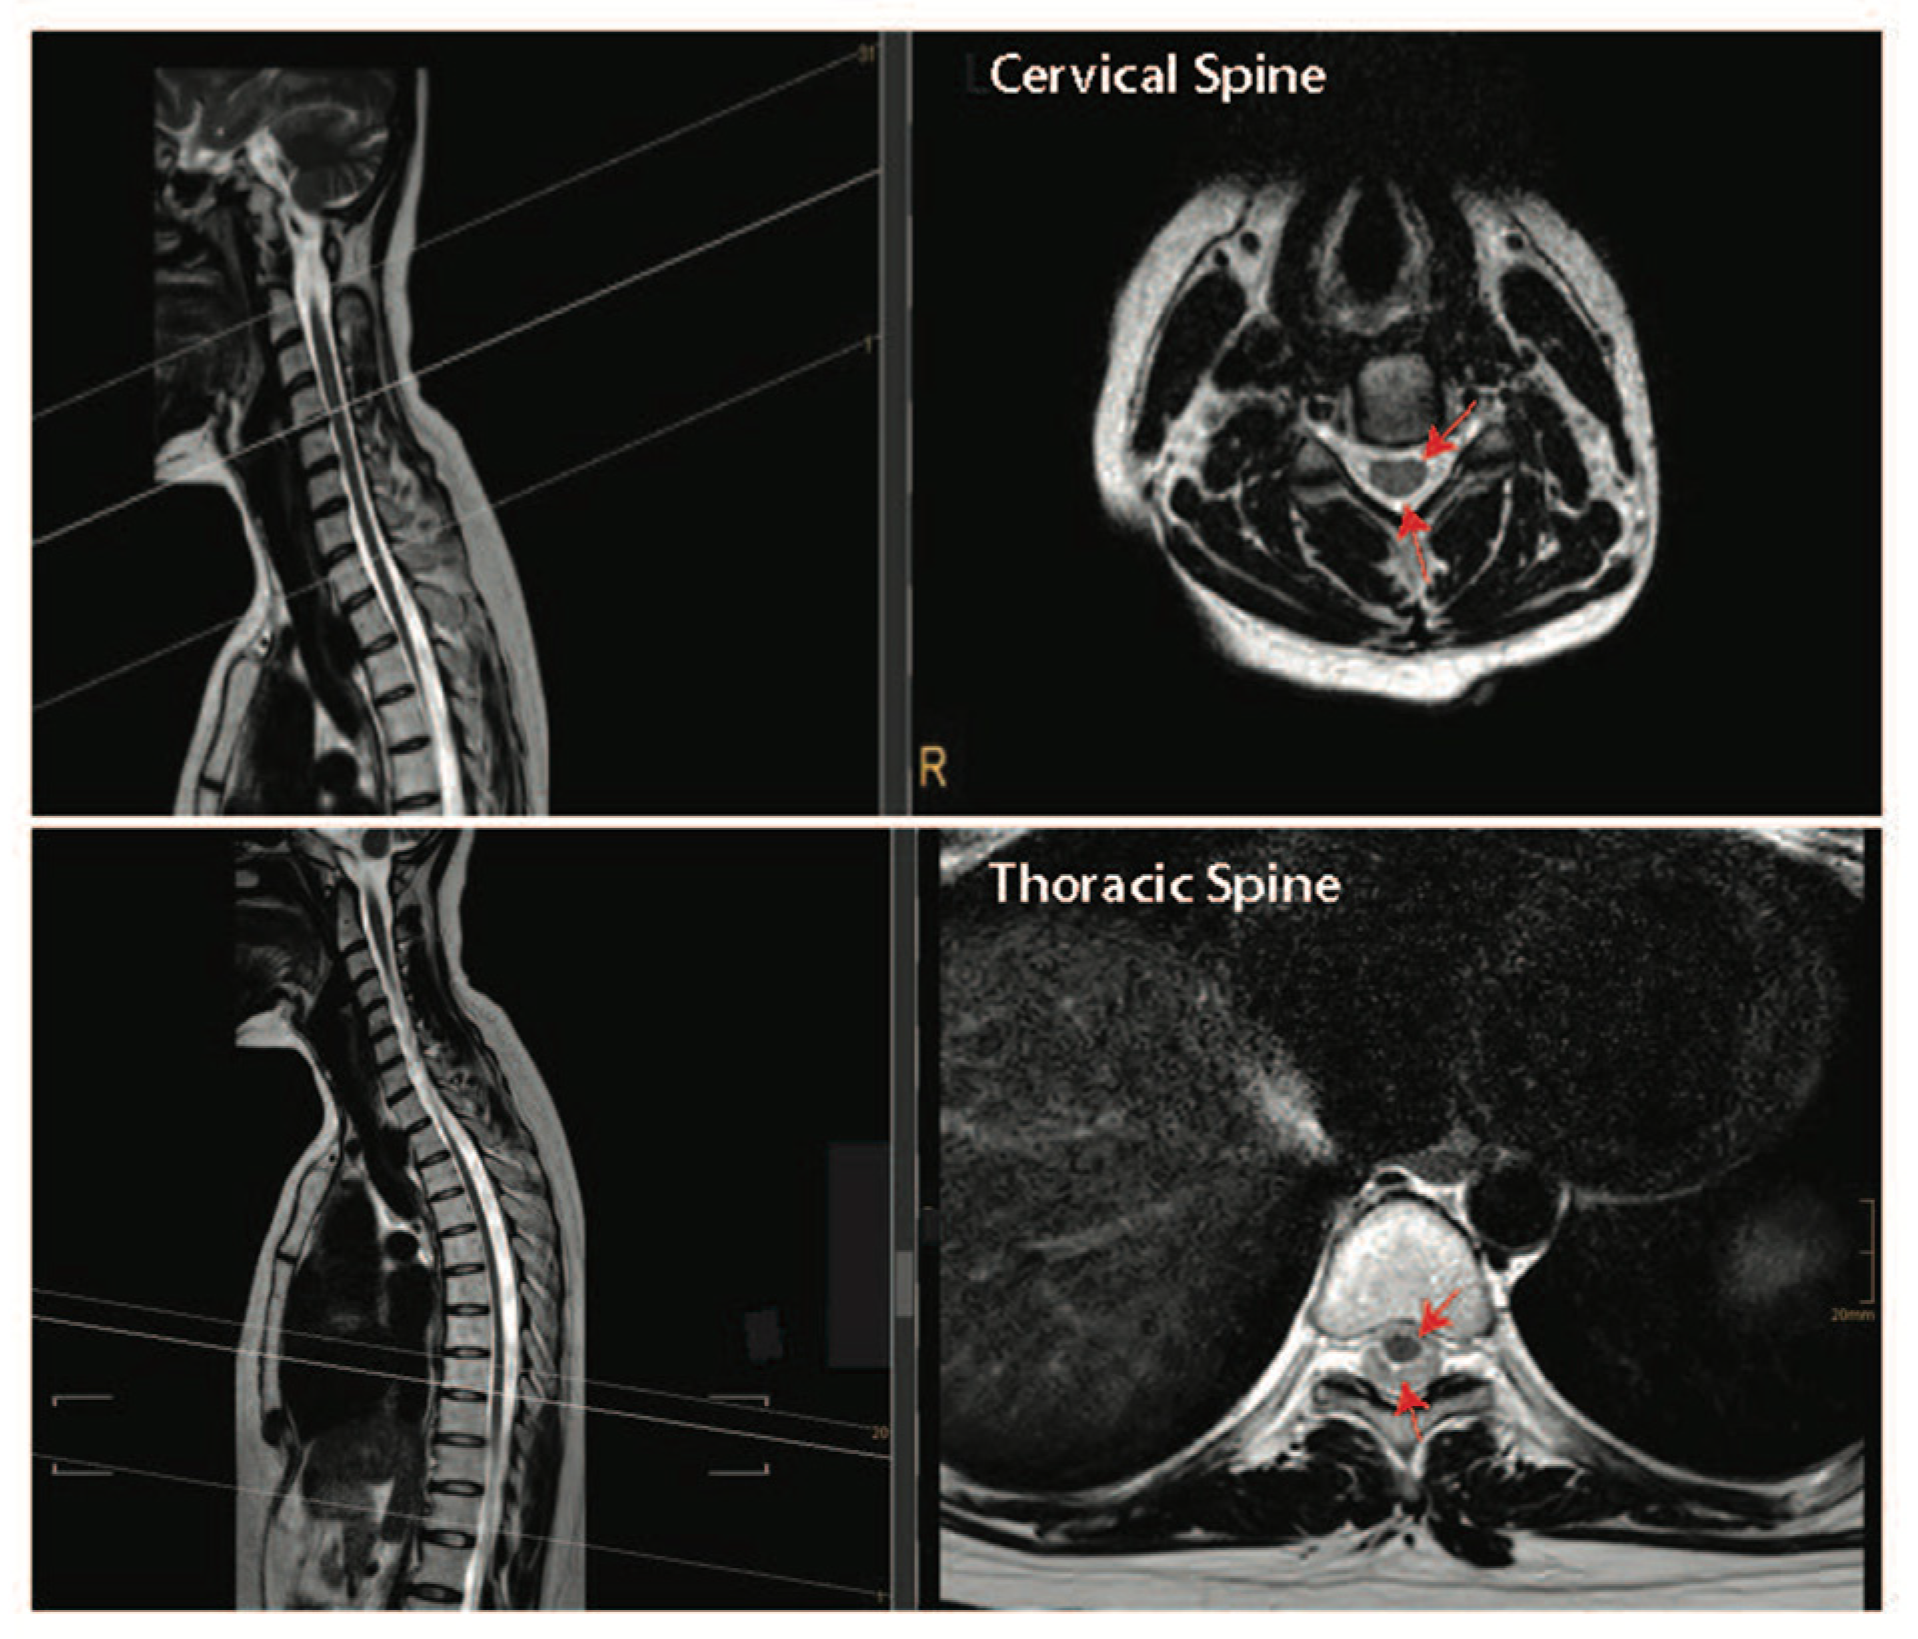

Figure 4.

Intact cervical and thoracic spinal cord tissue can float freely within the spinal column in humans. Top panel—T2-weighed sagittal and cross-sectional images of the cervical spine. Bottom panel—T2-weighed sagittal and cross-sectional images of the thoracic spine. Dark structures where the red arrows are pointing are the spinal cord tissue and the lighter areas depict cerebral spinal fluid-filled subarachnoid space. Images are courtesy of Dr. Tobias Prasse.

Together, the pre-clinical and clinical data presented above suggest that performing both a durotomy with a piotomy may be more effective than a durotomy alone at reducing the raised ISP after acute SCI. However, the highly invasive nature of durotomies and piotomies introduces risks, including further mechanical damage to the spinal cord, infections, excessive ISP reduction, CSF leaks and fistulas, hemorrhage, and pseudo-meningoceles, thereby necessitating a thorough risk–benefit analysis that accounts for patient-specific injury pathologies [119]. For example, the risk–benefit analysis for durotomy and piotomy likely depends on the SCI level [112]. Specifically, the human spinal cord tissue occupies only 50% of the subdural space within the thoracic spinal cord, while it occupies about 90% of the subdural space within the cervical spinal cord (Figure 4). Given the larger space in which the spinal cord can expand without dural compression at the thoracic level [120], benefits associated with a durotomy and/or piotomy may be more pronounced for cervical level injuries, where more severe swelling would lead to stronger cord compression. Furthermore, as discussed above, performing DS within the acute phase of SCI (within 72 h) appears to facilitate significant functional recovery [97,100,115,121].